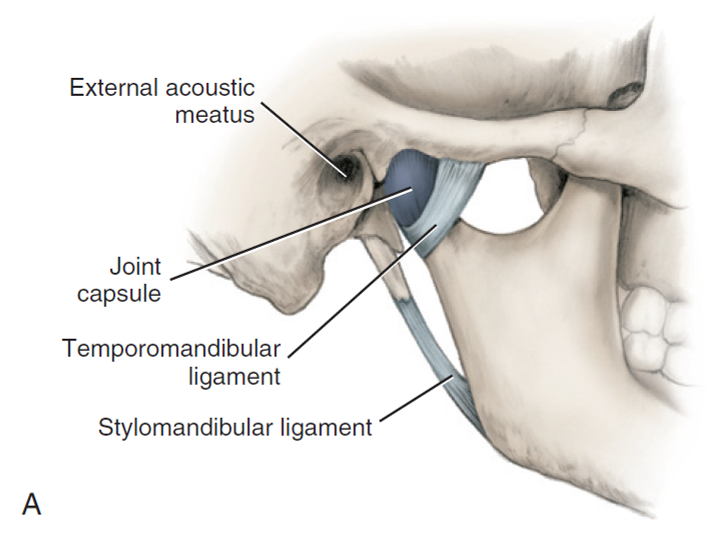

TMJ

Join capsule

Articular eminence 到 articular fossa

Joint disk

-

分成 Ant. band(2mm), Central intermediate zone(1mm),

Post. band(3mm) -

Dense fiber CT,無神經血管

-

Lower division 連到 condylar neck 的 lat.,med. poles

-

Upper division 連到 Temporal bone 的 postglenoid process

collateral ligament

retrodiskal tissues

有神經血管,分秘 Synovial fluid 到 Synovial cavity

- Superior retrodiskal lamina:elastic fibers,接到 tympanic plate,限制平行移動

- Inferior retrodiskal lamina:Collagen fibers,將 disc 接到 condyle,限制旋轉移動

JAW movement

- 旋轉: 下顎離上門牙2.5cm

- 平移: disc-condyle complex 沿 articular eminence 滑動,可再往前張開約 1.5 公分